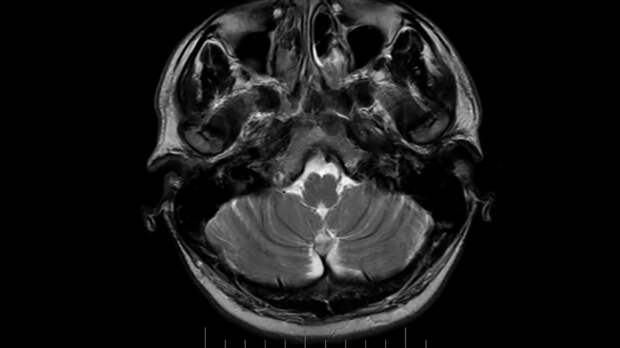

Фото: Скриншот видео Рен тв

Ученые сделали МРТ головного мозга людей, уверенных в своем счастье, и выяснили, что за эту эмоцию отвечает лимбическая система. У счастливчиков увеличивается количество серого вещества во внутренней части теменной коры правого полушария. Впрочем, даже исследователей с умными машинами можно обмануть.